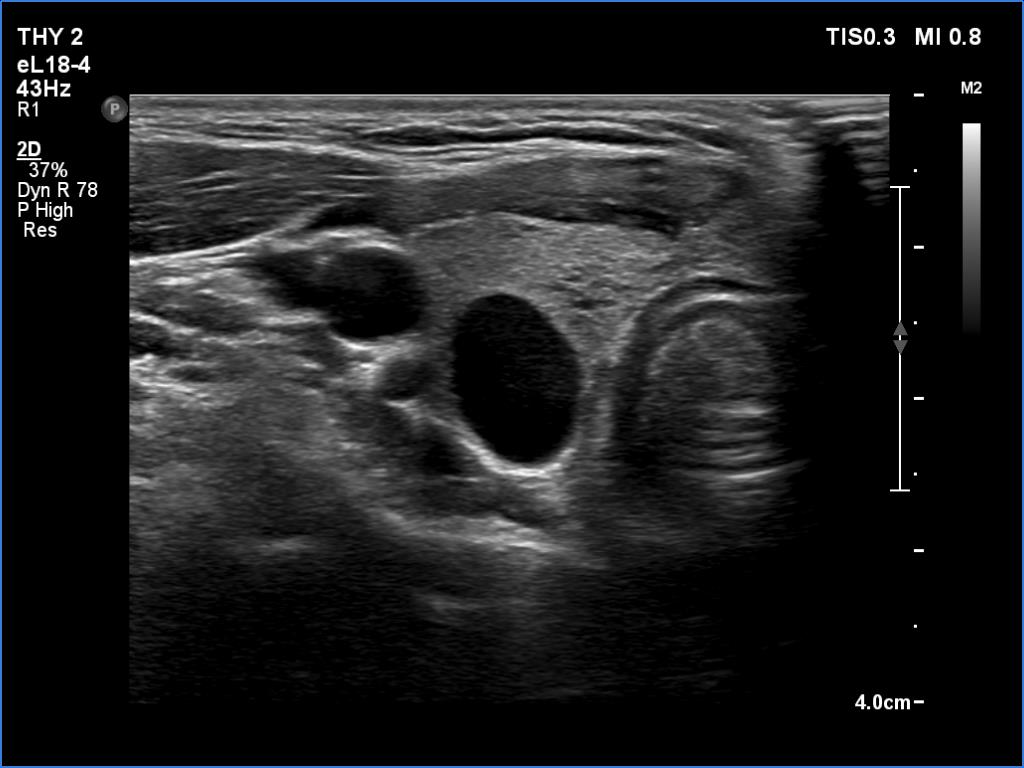

Transverse scan |

Longitudinal scan |

According to the EU-TIRADS, this lesion cannot be regarded as a purely cystic nodule due to the presence of wall-thickening (yellow arrows). The EU-TIRADS defines this lesion as an EU-TIRADS 3 nodule.